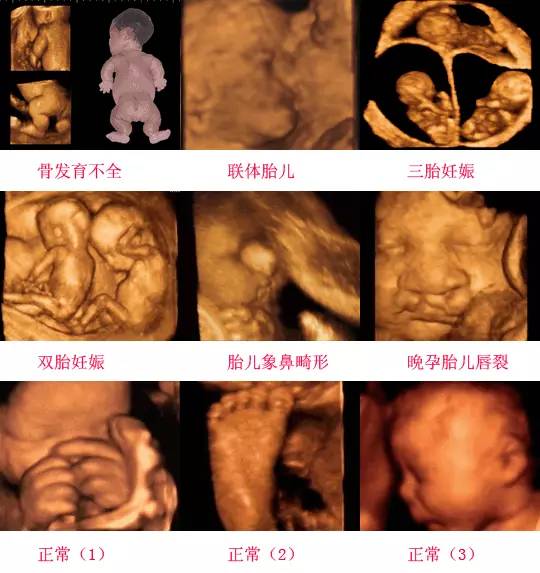

四維彩超是一種先進(jìn)的醫(yī)學(xué)影像技術(shù),通過實(shí)時(shí)觀察胎兒在母體內(nèi)的活動情況,為醫(yī)生提供了豐富的診斷信息,在四維彩超下,我們可以清晰地觀察到胎兒的蛋蛋(睪丸)的形態(tài)、位置和大小等特征,胎兒蛋蛋是男性生殖系統(tǒng)的重要組成部分,對于胎兒的生長發(fā)育具有重要意義。

在四維彩超下,胎兒蛋蛋呈現(xiàn)出特定的形態(tài)和外觀,通常情況下,胎兒蛋蛋呈現(xiàn)出圓形或橢圓形,表面光滑,內(nèi)部回聲均勻,隨著胎兒的發(fā)育,蛋蛋會逐漸增大,并呈現(xiàn)出明顯的性別特征,醫(yī)生可以通過四維彩超技術(shù),對胎兒蛋蛋的大小、形態(tài)和位置進(jìn)行評估,以判斷胎兒生殖系統(tǒng)的健康狀況。

胎兒蛋蛋的發(fā)育是一個(gè)復(fù)雜的過程,受到多種因素的影響,在胎兒發(fā)育的早期階段,蛋蛋位于腹腔內(nèi),隨著胎兒的生長發(fā)育,蛋蛋逐漸下降至陰囊,這個(gè)過程受到激素、遺傳和環(huán)境等多種因素的影響,在四維彩超的觀測下,我們可以實(shí)時(shí)了解胎兒蛋蛋的發(fā)育過程,及時(shí)發(fā)現(xiàn)異常情況并采取相應(yīng)的治療措施。

四維彩超技術(shù)在評估胎兒蛋蛋發(fā)育方面具有重要意義,通過四維彩超,醫(yī)生可以實(shí)時(shí)觀察胎兒蛋蛋的形態(tài)、位置和大小等特征,了解胎兒生殖系統(tǒng)的發(fā)育情況,四維彩超還可以幫助醫(yī)生發(fā)現(xiàn)可能的異常情況,如睪丸未降、睪丸囊腫等,為及時(shí)采取治療措施提供依據(jù)。